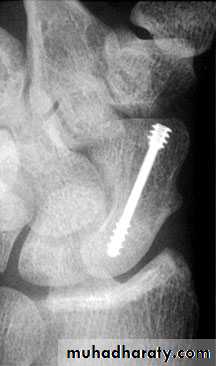

Displaced fracture: open reduction and internal fixation.

Surgical treatment